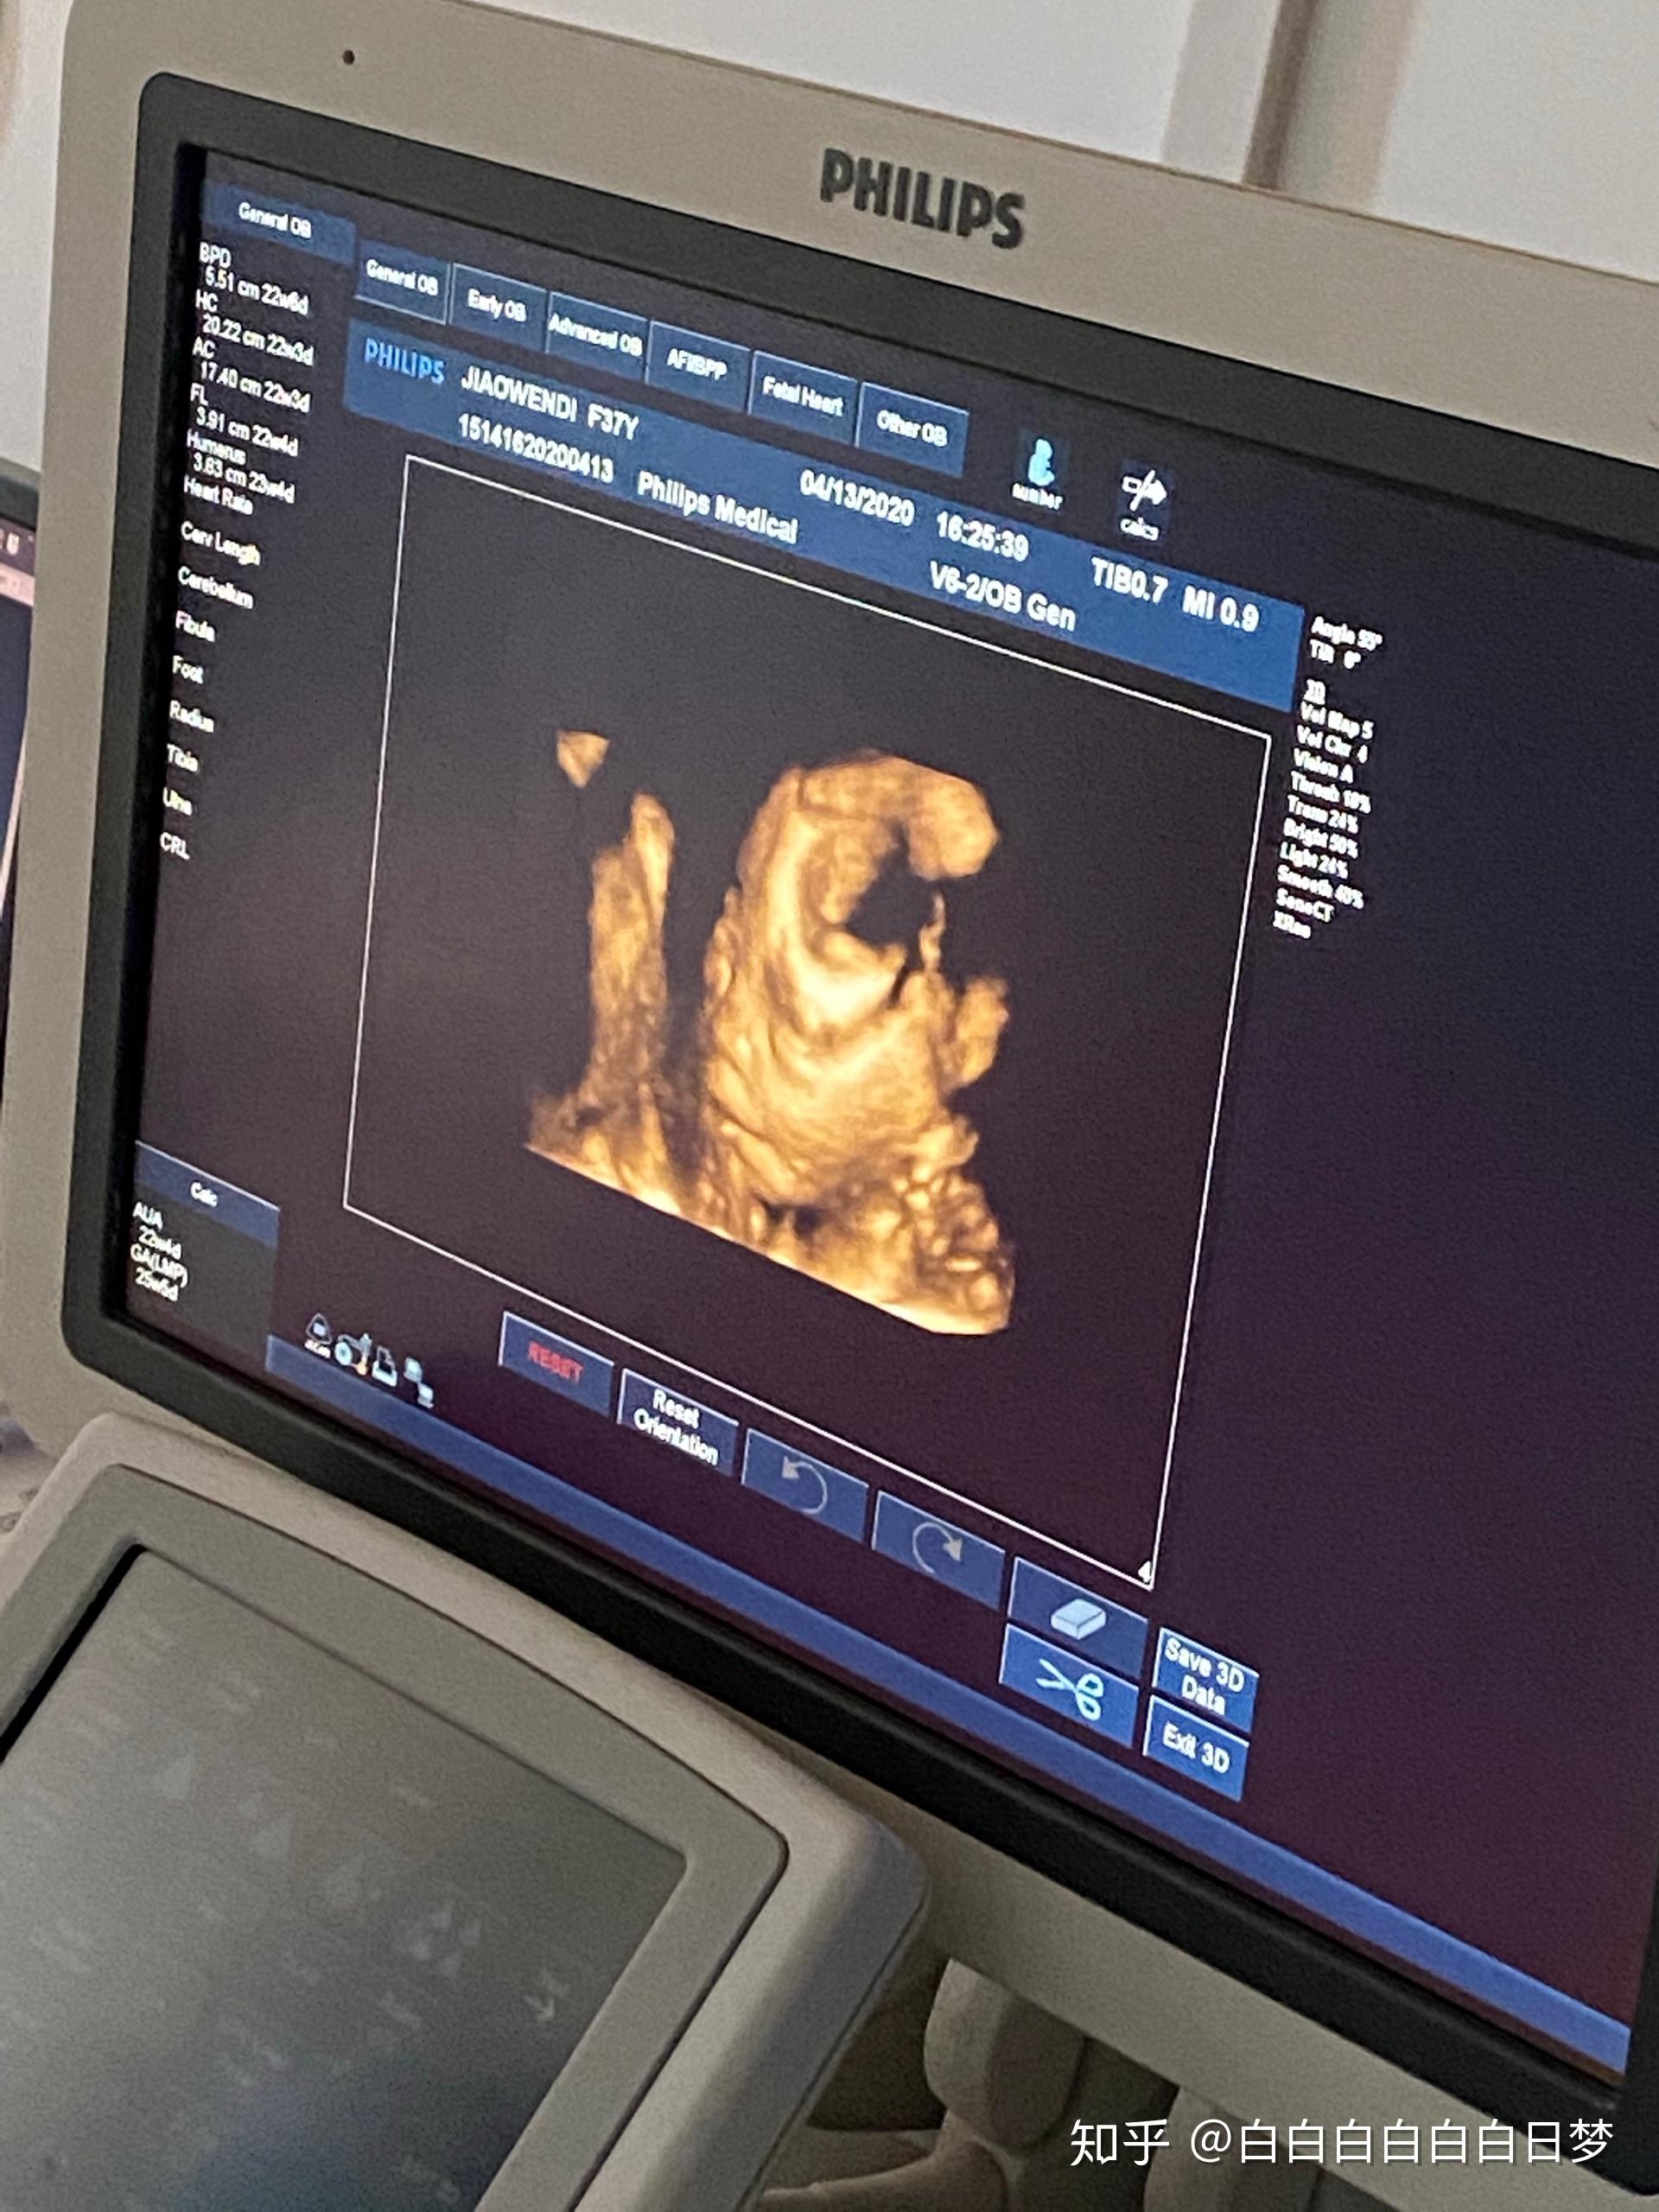

四维彩超宝宝特别配合非常清晰

你第一次看到宝宝的四维彩超照片是什么感觉

你第一次看到宝宝的四维彩超照片,是什么感觉?